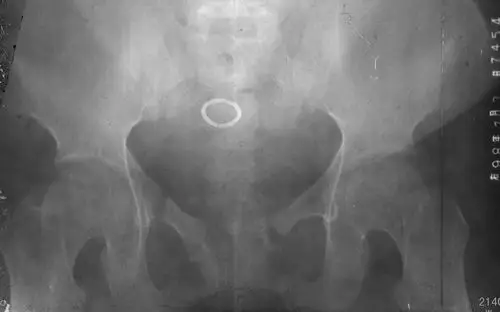

骶尾骨骨折易误诊为病变的3种假象,一旦遇到需警惕!